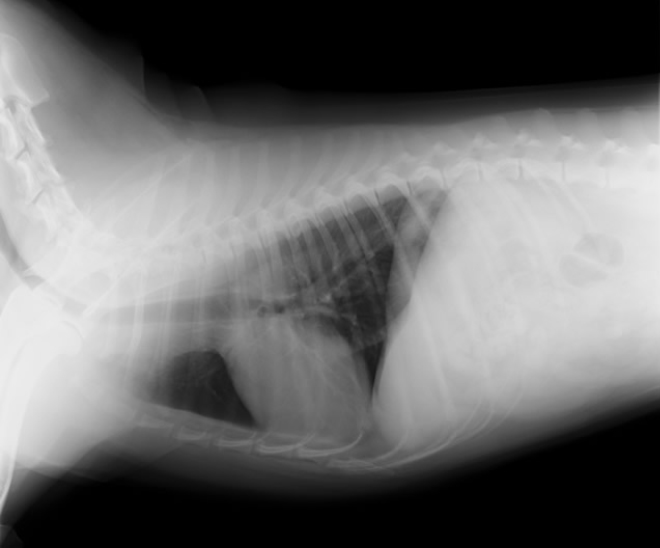

胸部レントゲン検査

X線により心拡大の有無、気管や肺の異常・病変の有無、肝臓うっ血の有無など、内臓の外観の評価を行います。2~3方向から撮影することによって多角的に異常を検出します。

心臓疾患による外観の異常は、たとえば咳の症状が見られた場合には肺や気管にも変化が見られるなど、心臓以外にも現れることがあります。胸部レントゲン検査はスクリーニング検査としても、診断の確度を上げる意味でも重要です。また、犬猫の心臓疾患は肺水腫や胸水を二次的に引き起こすことが多いため、その確認をする上でも有用となります。

正常心陰影(小型犬)

心拡大、肺水腫(小型犬)